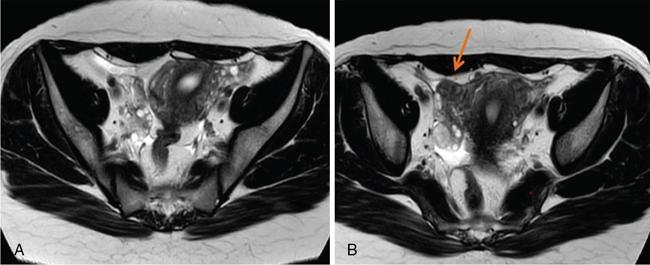

MÜLLERIAN DUCT ANOMALIES Rajani Gorantla Müllerian ducts are a pair of tubular structures that give rise to uterus, cervix, fallopian tubes and upper two-thirds of vagina. Disruption or failure of normal development can result in occurrence of Müllerian duct anomalies (MDAs). These are commonly associated with other congenital anomalies of urinary tract and ovaries due to the close relationship between the development of mesonephric and paramesonephric ducts; few patients also have associated skeletal system anomalies. The prevalence of MDAs in an unselected population was 5.5%; 8% among the infertile women, 12.3% in women with a history of recurrent pregnancy loss and 24.5% in women with miscarriage and infertility. Most of the patients with MDAs are asymptomatic and found incidentally on imaging for any other gynaecological problems, in evaluation of a patient with renal, skeletal or abdominal wall abnormalities. In symptomatic women, complains are related to the type, severity, obstructive anomaly or nonobstructive anomaly. The symptoms can be obstetric or gynaecological related, includes recurrent spontaneous abortions, infertility, preterm labour, intrauterine growth restriction and abnormal foetal lie. Few adolescent girls may present with primary amenorrhoea, hypomenorrhoea, abnormal vaginal bleeding, cyclical pain and mass. Rarely they can present with pelvic inflammatory disease with abnormal vaginal discharge, dyspareunia and urinary tract infections. The female reproductive system develops from a pair of Müllerian or paramesonephric ducts, urogenital sinus and vaginal plate. The ovaries develop separately from the primordial ridge. It is of great importance to understand the normal stages of development, as failure or interruption of any of these stages can lead to a simple to complex spectrum of anomalies. The three stages of Müllerian duct development include: At 6–10 weeks of gestation age, two paired Müllerian ducts and Wolffian ducts formation occurs. When Y chromosome factor (testicular determining factor) is absent, the Wolffian ducts undergo degeneration. The Müllerian ducts further elongate caudally and cross the Wolffian ducts to fuse in the midline. At 10–13 weeks of gestation age, caudal and lateral fusion of the two Müllerian ducts forms primitive uterovaginal canal, which is possessed of solid tissue initially located side by side and further internal canalization leads to the formation of two channels/canals divided by a septum. At this stage, there is reabsorption of the caudal septum and forms single cervical canal and vagina lumen. In around 15–20 weeks of gestation age, complete resorption of the septum takes place in a caudocranial direction from the isthmus to fundus and development of single endometrial cavity results. The fused caudal part of Müllerian ducts gives rise to the uterus, cervix and upper two-thirds of vagina; the unfused cranial part forms the fallopian tubes (Fig. 11.14.1.1). The lower vagina develops from the urogenital sinus, which is separated from the rectum by urorectal septum around 7 weeks of gestation age. The primitive uterovaginal canal embeds into the dorsal wall of urogenital sinus and forms Muller’s tubercle. Around 13 weeks of gestation, two solid masses known as sinovaginal bulbs originate from the upper part of the Muller’s tubercle, further proliferate into the caudal end of the uterovaginal canal to become a solid vaginal plate. Later canalization or degeneration of the central cells of the vaginal plate forms the lower vagina, which is usually completed by 20 weeks’ gestation. The vertical fusion of the upper and lower vagina occurs with resorption of tissue in between and forms single vaginal cavity (Fig. 11.14.1.2). The vaginal lumen is separated from the urogenital sinus by the hymenal membrane. Just before birth, the hymen normally ruptures due to retrogression of the central epithelial cells. However, a thin fold of mucous membrane persists around the vaginal introitus. The ovaries develop separately from migration of primordial germ cells to the genital ridge. Ureteric buds develop separately and concurrently. So renal anomalies are most commonly associated with MDAs with an association of 30%–50%. Various classification systems have been proposed over the past several decades to describe MDAs. Ideally, same classification system needs to be followed by a gynaecologist, surgeon and radiologist for better communication. Buttram and Gibbons classification was suggested in 1979, and it was based upon the level of failure in normal development and segregate the anomalies into groups with similar clinical manifestations, treatment, and prognosis for foetal salvage. According to Buttram and Gibbons, the uterine anomalies were classified into six classes as described in Table 11.14.1.1. The drawback is the lack of classification of vaginal and other anomalies separately. The ASRM (previously the American Fertility Society – AFS) classification system is the most widely accepted classification worldwide over the past years and was introduced in 1988. According to this classification, MDAs are classified into seven classes (class I to class VII) as mentioned in Table 11.14.1.2. However, several limitations have been described by Grimbizis and Campo in 2010 (Fig. 11.14.1.3). The drawbacks of the ASRM classification system are as follows: Hence in 2016, an updated classification of uterine septum, that is ASRM-2016 was proposed and officially approved morphometric criteria are given for distinguishing between septate, normal/arcuate and bicornuate uteri (Table 11.14.1.3). The VCUAM classification was proposed in the year 2005. The main concern is to provide a simple, systematic, clinical classification in addition to providing a precise reflection of the entire malformation. The female genital organs were divided into the following subgroups in accordance with the anatomy: vagina (V), cervix (C), uterus (U) and adnexa (A). Associated malformations were assigned to a subgroup (M) relative to each specific organ. The disadvantage is due to its inherent complexity, and more than 56,700 individual combinations of anomalies are possible. ESHRE and ESGE established a common working group named CONgenital UTerine Anomalies (CONUTA) in order to devise an improved classification system (Table 11.14.1.4). It was published in 2013. Anatomy is the basis for systemic categorization of the MDAs. The subclasses are divided by the different degrees of uterine deformity and their clinical significance (Fig. 11.14.1.4). Cervical and vaginal anomalies are classified into independent supplementary subclasses (Figs. 11.14.1.5–11.14.1.6). For most of the clinicians, it helped as starting point for the development of guidelines for their diagnosis and treatment. The malformations are graded according to severity, U0–U5, C0–C4 and V0–V4, with U5, C4 and V4 being more severe. Class U3 incorporates bicorporeal fusion defects (didelphys and bicornuate) as this was considered as a more functional mode of classification. Arcuate uterus was not included separately, but this is categorized under normal variant into class U1c. Recent studies have demonstrated that the ESHRE/ESGE system provides an effective and comprehensive classification for almost all the currently known MDAs and overcomes the limits of previous classifications. However, there is a relative overdiagnosis of septate uterus with the application of ESHRE–ESGE criteria has been reported and which potentially might lead to unnecessary surgical overtreatment. C0 C1 C2 Normal cervix Septate cervix Double ‘normal’ cervix C3 C4 Unilateral cervical aplasia Cervical aplasia U4 V0 V1 V2 V3 Normal vagina Longitudinal nonobstructing vaginal septum Longitudinal obstructing vaginal septum Transverse vaginal septum and/or imperforate hymen V4 Vaginal aplasia C MDAs’ characterization and classification is of great significance, as the treatment is determined by the type and severity of abnormality. The various imaging modalities available include: HSG was the most recognized imaging modality, earlier to the development of the ultrasonography (USG) and MRI. It is an invasive fluoroscopic-guided procedure for uterine and tubal assessment, and is performed during the midproliferative phase of the cycle, ideally between days 7 and 10 of the cycle when endometrium is thin. Fluoroscopic spot images obtained to evaluate uterine configuration, uterine filling defects and fallopian tube patency. HSG allows evaluation of only the component of the uterine cavity that communicates with the cervix. The anatomic information about myometrium and external fundal contour will not be provided by HSG. The diagnostic criteria used to diagnose MDAs on HSG include: HSG findings of different MDAs are described in Table 11.14.1.5 and Fig. 11.14.1.10. Virtual HSG is a noninvasive technique performed by using a computed tomography (CT) scanner, done 45 s after the contrast material instillation begins. Contraindications are similar to those for HSG and include pregnancy and active pelvic infection. There is no necessity for retraction of the uterus or manipulation of the cervix. The procedure is quick, easy and prophylactic administration of antibiotics is not required. The use of a power injector helps to ensure a steady low pressure of instillation. The procedure is less painful, more comfortable and easily tolerated by patients than conventional HSG. Radiation exposure sometimes requires cervical clamping, which may result in complications such as bleeding and infection. Transabdominal pelvic ultrasound can diagnose uterine anomalies with accuracy rate of 47%. Two-dimensional transvaginal ultrasound (TVUS) has high sensitivity and specificity than transabdominal study and provided some information about external and internal fundal contours. The detection rate is high if the scan is performed in secretory phase due to better visualization of endometrium. Three-dimensional USG shows great accuracy than 2D USG in evaluation of the uterine morphology. The technique of 3D USG varies with different vendors. It displays both the external and internal fundal contours and lower uterine segment by acquisition of single coronal view of uterus (c-view) (Fig. 11.14.1.11). The only disadvantage is that it is transvaginal study and shall not be done in paediatric age group and sexually inactive women. Three-dimensional TVUS has become the first line of screening tool in most of the infertility clinics as it is noninvasive, faster, repeatable, allows storage of volume data and has multiplanar capability for systematic evaluation of the uterine and cervical cavities. The salient features of various Müllerian anomalies on 3D USG are described in Table 11.14.1.6 with images. Three-dimensional ultrasound is combined with sonosalpingography in this technique and provides better delineation of the uterine morphology. It is a less invasive procedure done in proliferative phase with instillation of saline into the uterine cavity and assessment of the uterus will be done. MRI is a universally accepted imaging modality in the documentation of MDAs and accuracy rate of 100% have been reported. MRI provides excellent delineation of both the internal and external uterine anatomies. T2-weighted (T2W) images are the mainstay of pelvic imaging and are performed without fat suppression. T1-weighted (T1W) images are mainly for the haemorrhagic content. The disadvantages of MRI include time-consuming procedure, not cost-effective, large body habitus, pacemakers, recent surgical history and claustrophobia. The current and proposed MRI protocol given by the European Society of Urology (ESUR-MRI protocol) intends a dedicated evaluation of MDAs as mentioned below (Fig. 11.14.1.12): Vaginal anomalies can be accurately diagnosed with the prior administration of the ultrasound gel, to distend vagina (Fig. 11.14.1.13). It will help in better diagnosis of complex vaginal anomalies, like vaginal septations or vaginal duplication. The normal MRI appearance of uterocervical canal and vagina are shown in Fig. 11.14.1.14. Uterine aplasia/hypoplasia/agenesis is class 1 MDA according to ASRM classification and U5 uterine anomaly according to ESHRE classification. It is a formation defect of the paramesonephric ducts with complete or segmental agenesis of uterus and vagina. The incidence rate is around 10%–15% of all MDAs and considered as the most severe form of uterine anomaly. Most of them have complete uterovaginal agenesis with no single completely developed uterine cavity and are associated with Mayer–Rokitansky–Küster–Hauser syndrome (MRKHS). Two types of this syndrome are depicted. The typical form or type A represents the absence or remnants of the uterus, cervix, upper two-thirds of vagina with normal ovaries and fallopian tube (Fig. 11.14.1.15). The atypical form or type B is associated with the abnormalities of the ovaries, fallopian tubes and genitourinary system (Fig. 11.14.1.16). In a few cases (approximately 10%), unilateral or bilateral uterine remnants and with or without endometrial cavity will be seen (Fig. 11.14.1.17). Most of them present with primary amenorrhoea due to complete uterovaginal agenesis and manifest as MRKHS. These patients have normal secondary sexual characteristics due to the preserved normal ovarian function and phenotype. If uterine remnants with functional cavity is present, will present with cyclical pain along with amenorrhoea due to cryptomenorrhoea and haematometra. USG is the first modality for identification of these anomalies, absence of uterus with normal ovaries is diagnostic. But, it is difficult to locate the uterine remnants and cavity due to small acoustic window. MRI is the gold standard and it classifies into uterovaginal agenesis and hypoplasia. If hypoplasia is identified, sagittal and axial sections are taken. These remnants are seen as T2 hypointense tubular structures, located in close relation to ovaries in the adnexa. Once we identify the uterine remnants, it is important to look for the functional endometrial cavity. These will have reduced endometrial and myometrial width. MRI can easily delineate the zonal anatomy due to its high soft tissue contrast resolution. The management of Müllerian agenesis consists of counselling for the patient and her parents. Some patients with MRKHS opt for creation of neovagina for normal sexual life. Various techniques are available. In the presence of a functional Müllerian remnant, regardless of whether it is communicating or not, medical suppression of menses can be initiated and should be followed by laparoscopic removal of the hypoplastic remnant. Unicornuate uterus or hemiuterus is defined as the unilateral uterine development and the contralateral Müllerian duct could be either partially formed or absent. It is a formation defect and the necessity to classify it in a different class than that of uterine agenesis, which is also a formation defect, is due to the existence of a fully developed functional uterine hemicavity. It is considered as class II anomaly according to ASRM classification and class U4 according to ESHRE classification. The frequency rate is around 20% of MDAs. Renal anomalies most often occur in association with unicornuate uterus and usually on the same side of uterine agenesis. Further unicornuate uterus is divided into two subclasses depending on the presence or absence of a functional rudimentary cavity in ESHRE classification: In ASRM classification, unicornuate uterus is divided into four subcategories: Mostly asymptomatic and presence of the noncommunicating uterine remnants will be identified at the time of infertility work up or caesarean section. If a functional cavity is present, the presentation is dysmenorrhoea or haematometra in an adolescent. The common obstetrics-related complications include abnormal foetal lie, intrauterine growth retardation, preterm delivery, placental abnormalities and uterine rupture. Gynaecological complications are ectopic pregnancy and endometriosis due to retrograde menstruation. On imaging, unicornuate uterus is seen as tubular and fusiform or banana-shaped structure at paramedian location, the endometrium is narrow and tapers to the apex with normal myometrial anatomy and reduced uterine volume. The rudimentary cavity or remnants are better depicted on 3D USG (Fig. 11.14.1.18) and MRI. However, MRI is superior to USG due to its high soft tissue resolution. The rudimentary cavity can communicate with main cavity or connected by fibrous band. The nonfunctioning cavity will be seen as T2 hypointense structure with loss of zonal anatomy (Figs 11.14.1.19 and 11.14.1.20), whereas the functioning cavity will show the deformed zonal anatomy (Fig. 11.14.1.21), and its complications like haematometra as T1/T2 hyperintense endometrial collection. Unicornuate uterus without rudimentary cavity does not require any procedure. But in the presence of communicating or noncommunicating rudimentary horn, surgical resection must be considered to prevent complications. Uterine didelphys is a class III MDA based on the ASRM classification and class U3b bicorporeal uterus according to ESHRE classification with an incidence rate of 5% among the uterine anomalies. It is a lateral fusion defect; results from complete failure of the Müllerian duct fusion. Two noncommunicating endometrial cavities with preserved zonal anatomy are seen with separate cervix. According to ESHRE classification, it is defined as external fundal indentation completely dividing the uterine corpus up to the level of external cervical os. It is most commonly associated with longitudinal vaginal septum in around 75% of cases. Some patients may show transverse vaginal septum and these will be obstructive or nonobstructive type. Renal anomalies are also commonly associated with uterine didelphys. Uterine didelphys is usually asymptomatic and diagnosed incidentally on pelvic examination or caesarean section. The uterine didelphys with obstructed vagina (Fig. 11.14.1.22) will present at adolescence as dysmenorrhoea, haematometrocolpos and haematosalpinx. Sometimes retrograde menstrual flow can cause endometriosis and pelvic adhesions. Obstetric-related complications include abortion/foetal growth restriction and poor pregnancy outcome. The uterine didelphys with obstructed hemivagina due to transverse vaginal septum and associated ipsilateral renal agenesis are the manifestations of the syndrome called obstructed hemivagina and ipsilateral renal agenesis anomaly/Herlyn–Werner–Wunderlich (HWW) syndrome (Fig. 11.14.1.23).